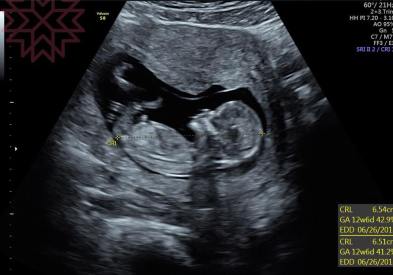

在十四週之前

我們是量頭臀圍

頭到屁股的長度

如圖

很清楚可以看到

腳是彎曲起來的

所以

怎麼量全長啦

別鬧了